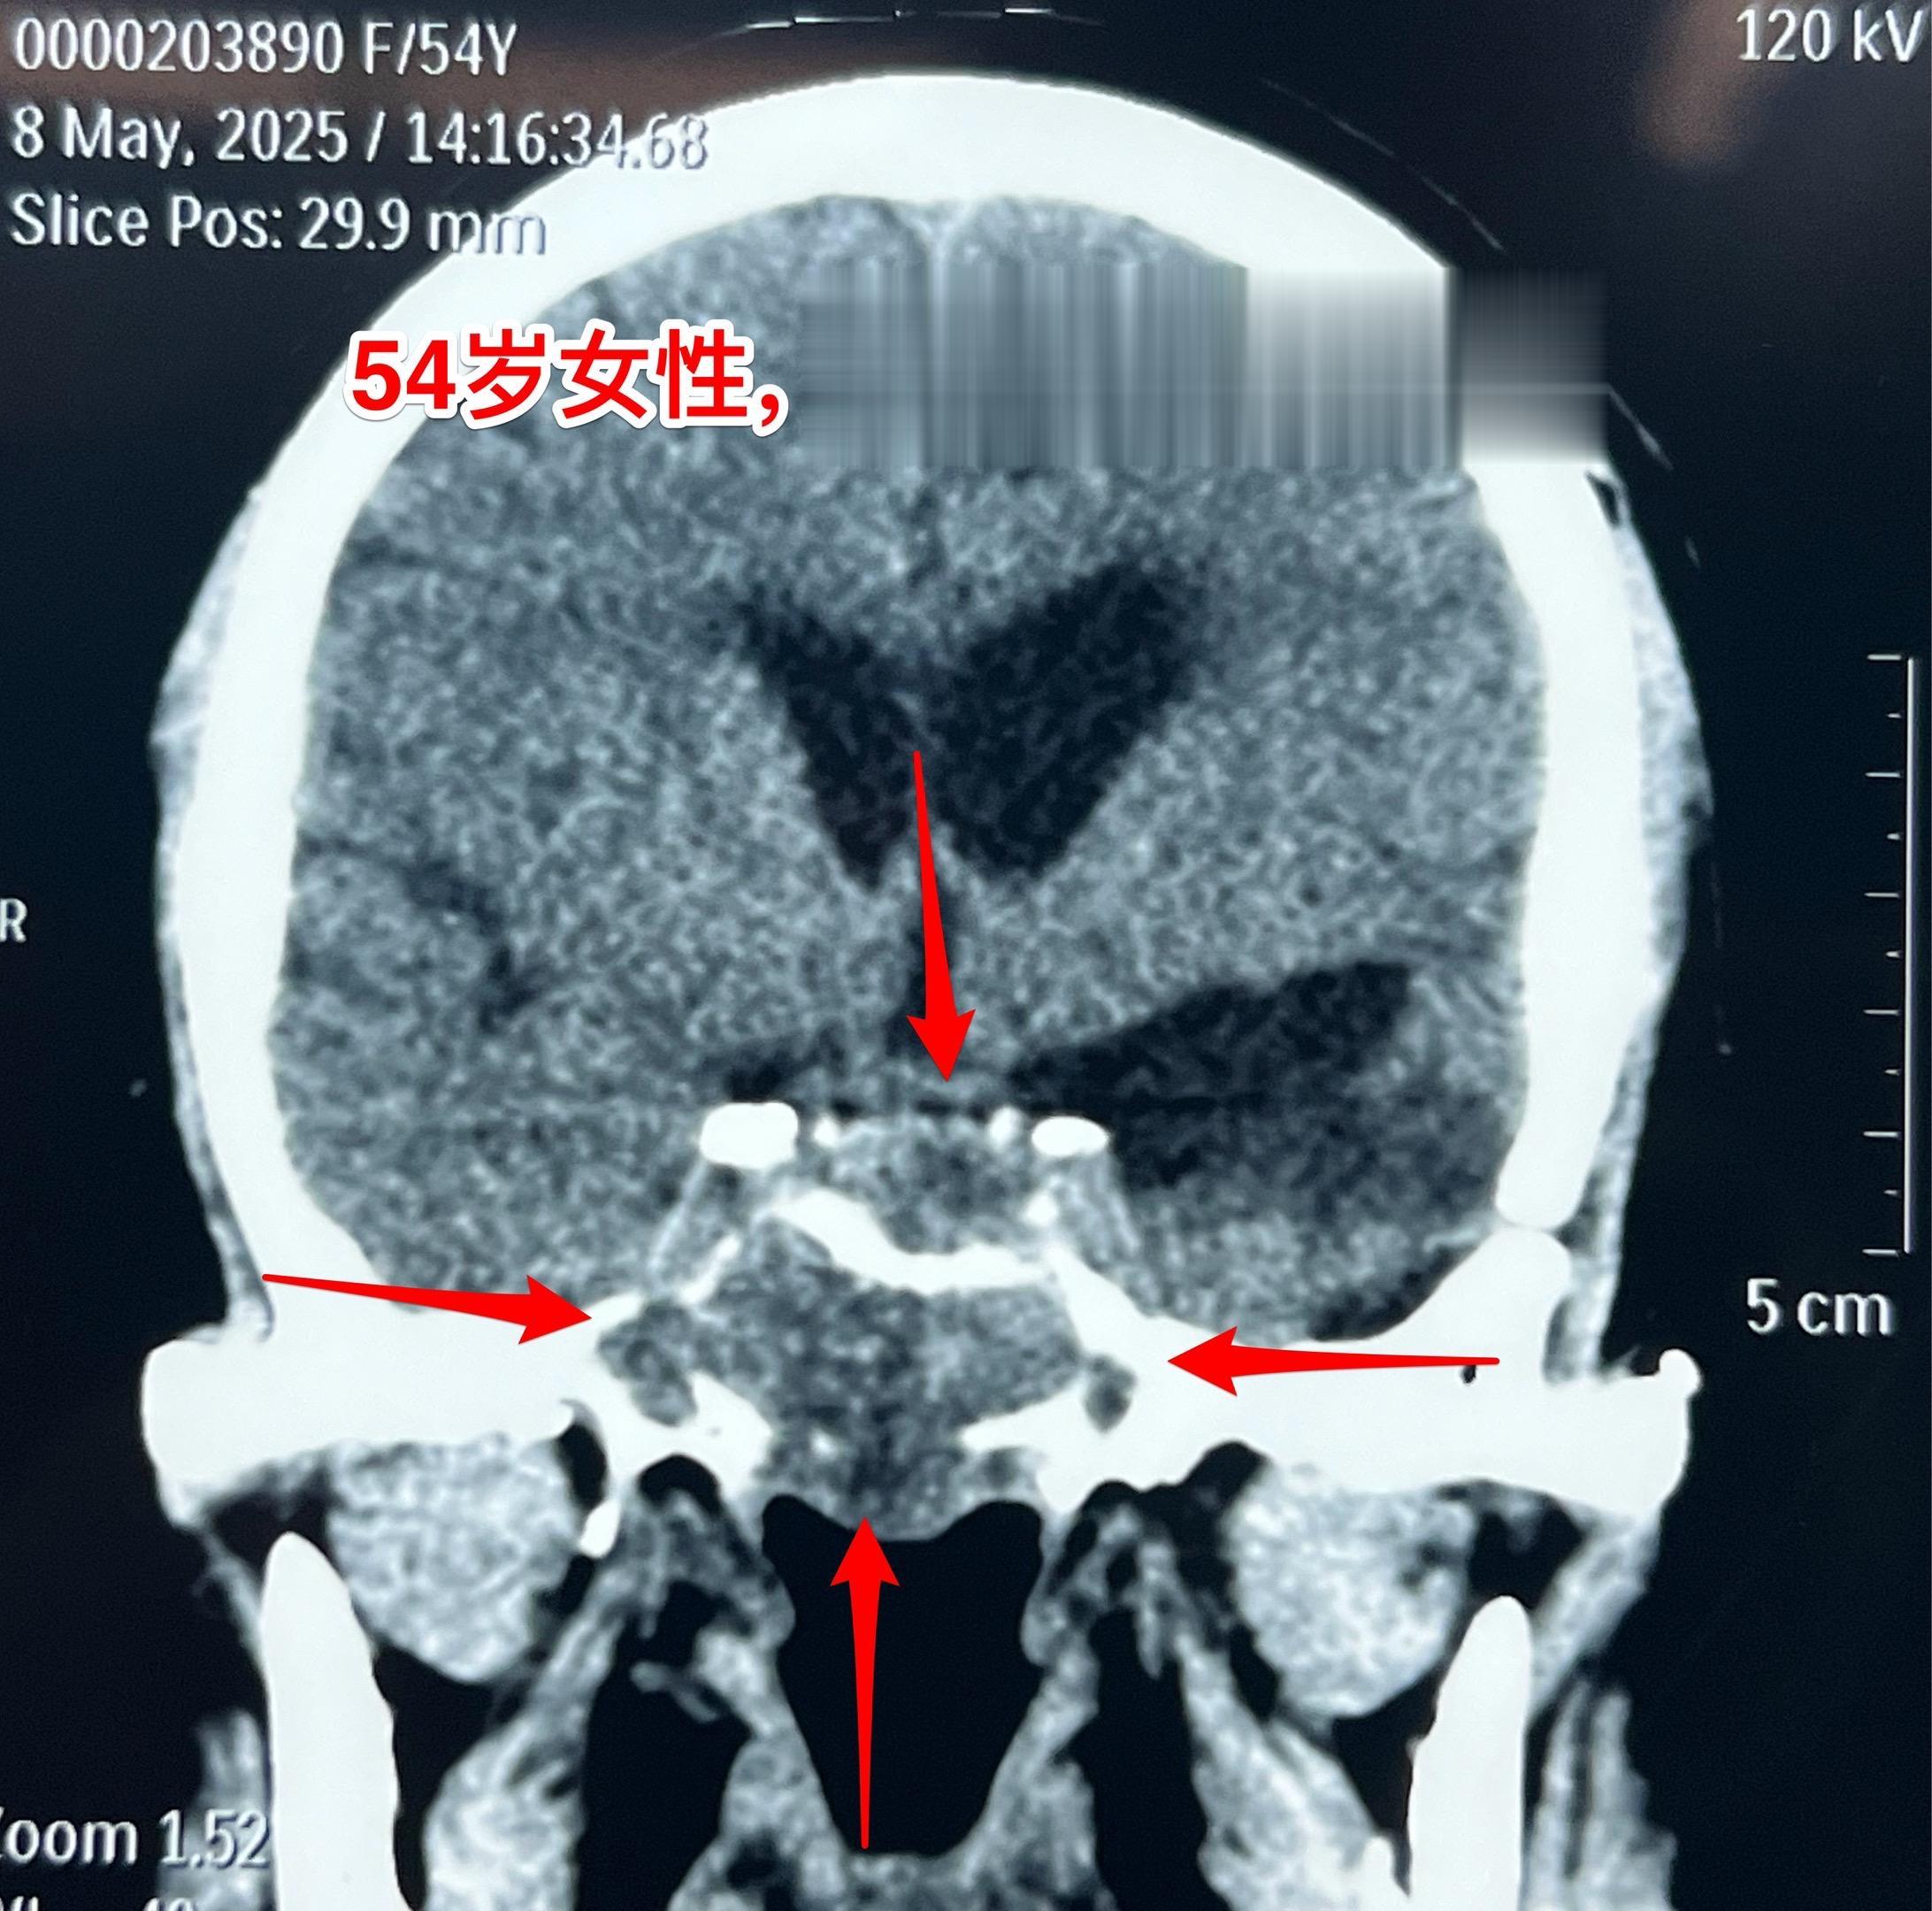

侵袭性垂体瘤第二次手术。54岁女性,2023年9月因垂体瘤作了第一次手术,是开颅手术,当时左眼视力下降。把颅内的肿瘤切除了,蝶窦内、海绵窦内的肿瘤没有动,计划二期手术。 2025年5月病人感觉左眼视力又有下降,来作第二次手术,磁共振、CT显示肿瘤巨大,是典型的侵袭性垂体瘤。这次只能采用经鼻手术了。昨天顺利完成手术。 今天病人没有出现脑脊液鼻漏症状,自感很轻松,精神好。